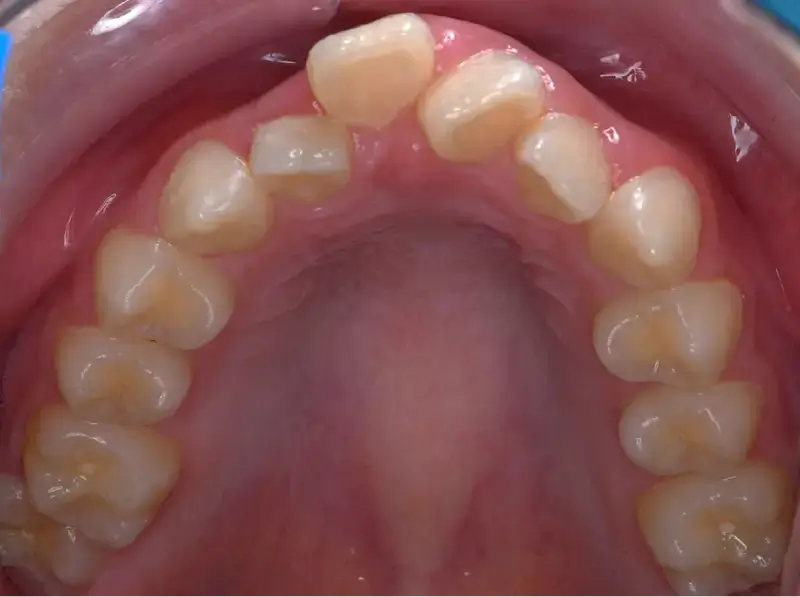

兒童早期矯正,又稱為「預防性矯正」或「第一階段矯正」,指的是在孩子乳牙或混合牙期(約7~10歲)時,就針對牙齒排列、咬合不正、牙弓發育等問題提前介入的矯正治療。 目的不只是「把牙齒排整齊」,更重要的是引導上下顎正常發育,減少未來拔牙、正顎手術的機率,讓恆牙有足夠空間健康萌發。

透過早期擴大牙弓、改善空間,能降低日後因擁擠而必須拔牙的情況。

相當於國小低至中年級,這時會開始進到乳牙換成恆牙的階段,也是牙齒移動速度快的時期,在這個階段接受矯正能夠擁有良好的矯正效率,因此也被定義為「兒童矯正的黃金期」。

增加牙弓空間幫助換牙